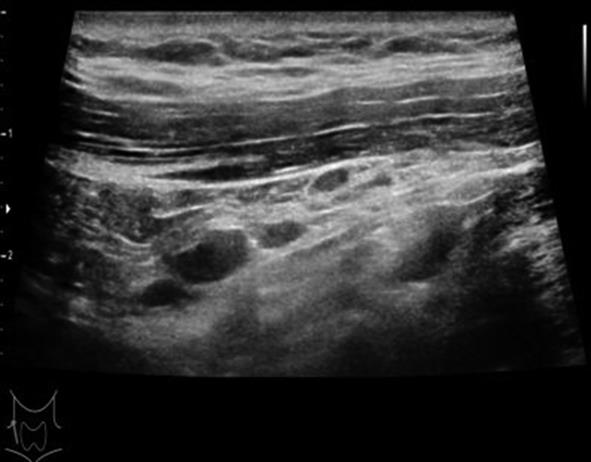

• 基于SEER数据库构建高危PTMC的诊断模型与验证

2023, 48(12):1418-1424. DOI: 10.13406/j.cnki.cyxb.003392

摘要 (71) HTML (47) PDF 1.64 M (177) 评论 (0) 收藏

摘要:目的 探讨高危甲状腺微小乳头状癌(papillary thyroid microcarcinoma,PTMC)的风险预测因子,构建可靠的列线图诊断模型并验证。方法 回顾性分析2004至2015年SEER数据库中手术治疗的PTMC患者(训练集)以及2020至2022年四川省人民医院甲状腺诊疗中心诊治的甲状腺微小结节患者(外部验证集)的临床病理及超声影像资料。验证集中,利用logistic回归分析高危PTMC的风险预测因子,构建列线图诊断模型并采用内部验证集和外部验证集分别进行验证。再根据术前超声影像学特征进行间接评估,探讨术前超声影像学特征预测高危PTMC的可行性与可靠性。结果 训练集纳入患者1 552例,外部验证集纳入患者516例。训练集中筛选出高危PTMC的独立危险因素为性别(男性)、年龄(≤55岁)、结节数目(多灶)、包膜侵犯,颈部淋巴结异常(P<0.05),构建出的列线图C指数为0.946。在训练集及外部验证集中,该列线图模型的预测结果与实际情况均具有较好的一致性。基于超声影像特征诊断高危PTMC的受试者工作特征(receiver operating characteristic,ROC)的曲线下面积(area under the curve,AUC)值为0.931(95%CI=0.910~0.953),与基于病理特征诊断的AUC值具有较高的一致性(κ=0.611,P<0.05)。结论 本研究构建的高危PTMC诊断模型具有较好的预测效应,利用术前超声影像学特征预测高危PTMC具有一定的临床可行性及临床应用价值。